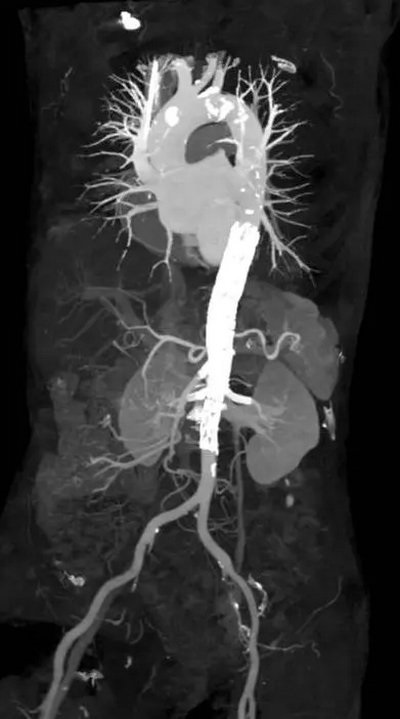

该患者的主动脉假性动脉瘤累及内脏区,病变十分罕见,一旦瘤体破裂患者即可休克猝死(图1)。由于其外科开放手术的复杂程度远超过单纯的肾下腹主动脉瘤,手术首先需要胸腹部联合切口,之后采用人工血管置换腹主动脉,还要重建腹腔干,肠系膜上动脉及双肾动脉。该手术不仅创伤巨大,难度巨大,还存在截瘫、肠缺血、肾缺血等诸多风险。但该患者身材瘦小,体质差,无法耐受手术创伤,因此该患者不适合开放手术。

▲ 图1